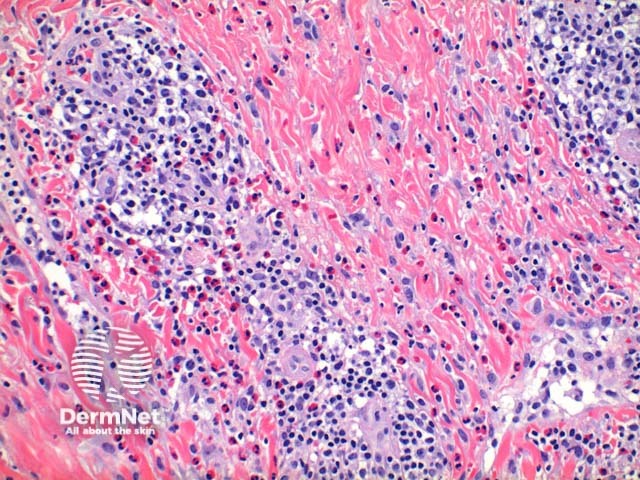

Scanning power view of scabies shows a pattern of an epidermal and wedge shaped dermal inflammatory process (Figure 1). The epidermis may show significant scale crust comprised of serous exudate, neutrophils, and eosinophils (Figure 2). There may be focal ulceration or erosion secondary to excoriation. The inflammatory infiltrate may show a wedge shaped or diffuse superficial and deep perivascular and interstitial pattern. Lymphocytes with numerous eosinophils are the rule with scattered superficial neutrophils seen in excoriated or impetiginised cases. Deep interstitial eosinophils are an important clue to an arthropod bite reaction (Figure 3).

Figure 3